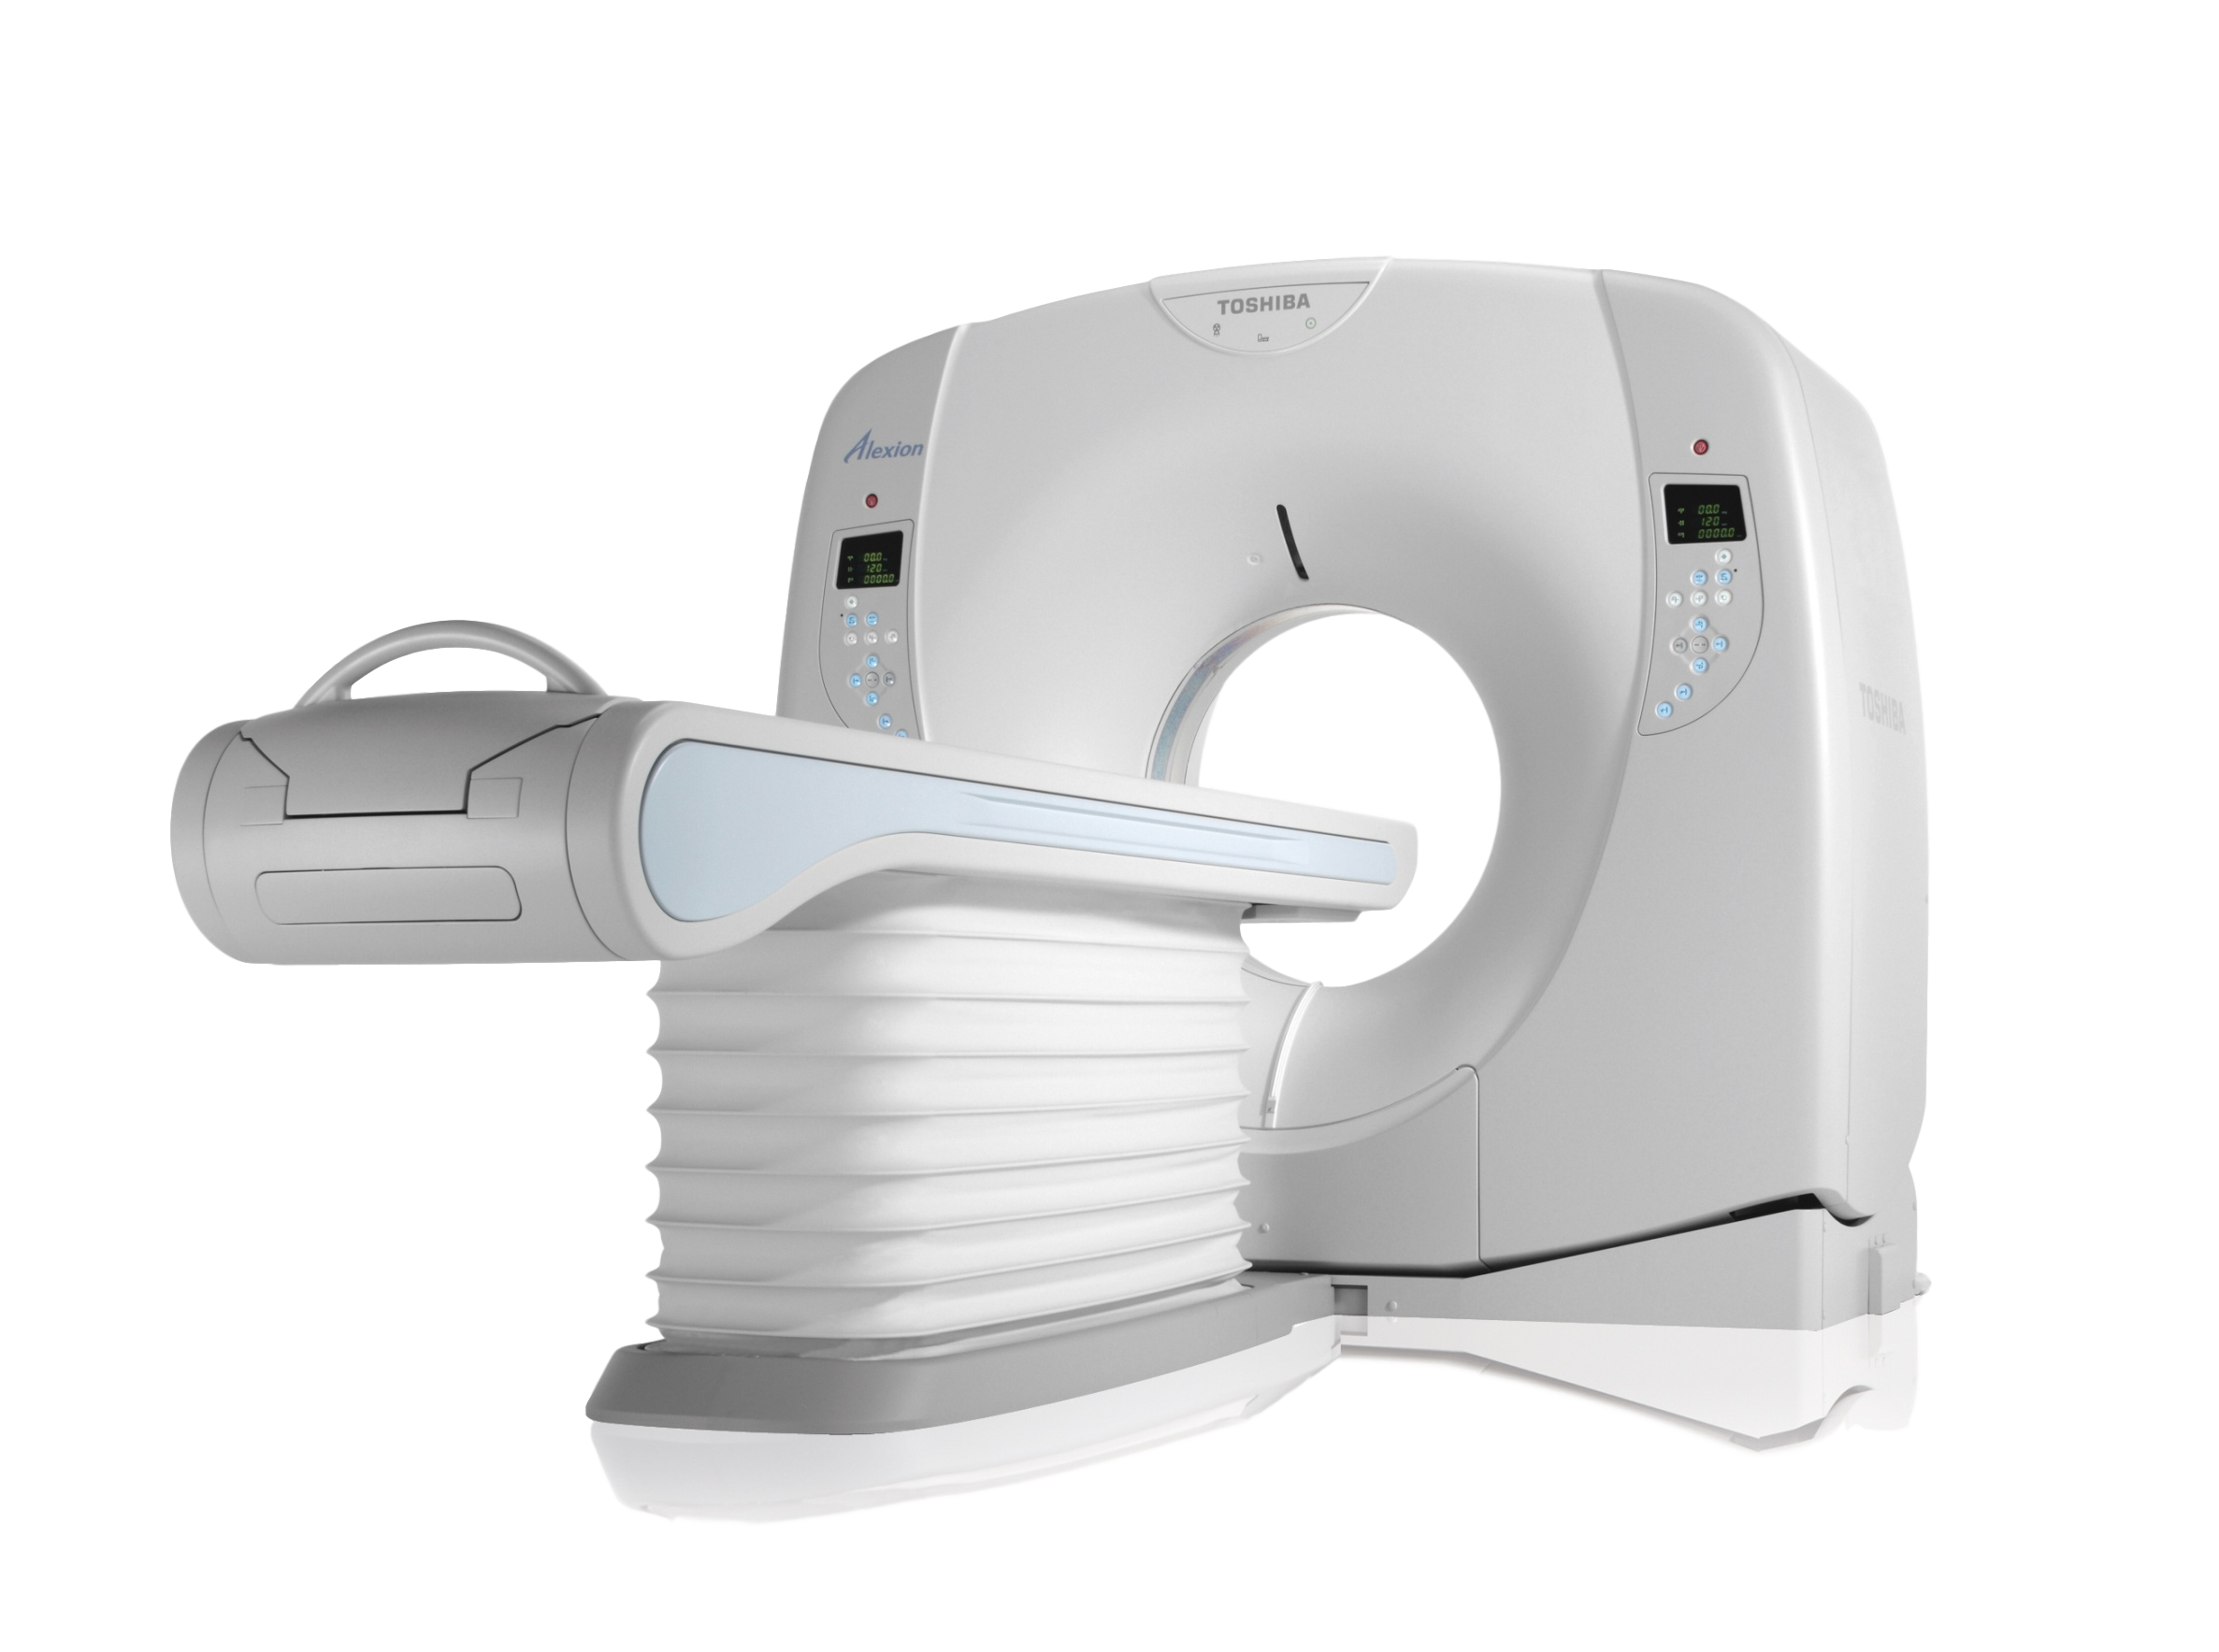

Серия КТ-сканеров Alexion 16 поддерживает множество передовых приложений, изначально разработанных для КТ-систем премиум-класса Canon Medical Systems. Приборы разработаны с использованием новейших аппаратных, программных и восстановительных технологий, которые позволяют достигать высоких диагностических результатов. Canon Medical Systems занимается разработкой и производством экологически безопасных приборов. Комплексная оптимизация энергопотребления всех компонентов системы снижает общие требования к энергопотреблению системы. Благодаря использованию энергосберегающих технологий, таких как автоматическое управление портальным вентилятором, энергопотребление в режиме ожидания снижается на 40% по сравнению с обычными системами.

Снижение дозы облучения - это основная задача Canon Medical Systems, поэтому серия Alexion включает в стандартную конфигурацию новейшую технологию снижения дозы.

Серия Alexion отличается высокой производительностью и требует небольших помещений, так как имеет площадь всего 10,4 м2. Частично благодаря гибким требованиям к размещению, серия Alexion может быть запущена и работать в удивительно короткие сроки.